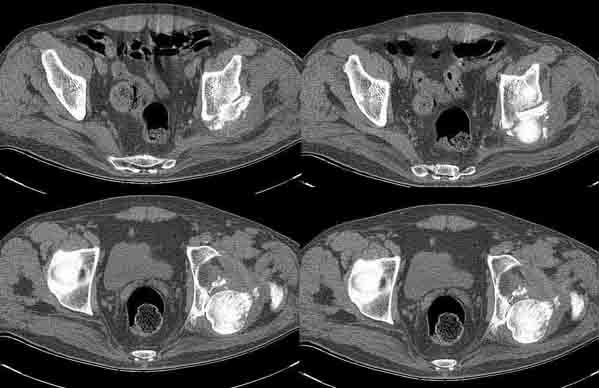

Больной Н. 54 лет. Поступил в подвздошным вывихом левого бедра. После попытки закрытого одномомендного вправления 2 мес. на скелетном вытяжении. На Rg контроле видимость вправления, на КТ - неустраненный вывих. По причине тяжелой соматической патологии открытое вправление и репозицию заднего края выполнить не представляется возможным. Вправление аппаратом внешней фиксации, КТ - этапах вправления - дефект заднего края. Что вы нам посоветуете по дальнейшей тактике? Больной Н. 54 лет. Диагноз: Закрытый оскольчатый перелом заднего края вертлужной впадины слева, подвздошный вывих левого бедра. Ушиб грудной клетки. ИБС. Стенокардия напряжения. ФКI-II. Постинфарктный кардиосклероз. Артериальная гипертония II степени, риск IV. НI. Состояние после аорто-коронарного шунтирования. Хронический бронхит. ДНI.Травма в результате ДТП. Больной лечился консервативно - закрытое одномоментное ручное вправление, фиксация скелетным вытяжением в течение 2 месяцев. На контрольных обзорных рентгенограммах таза в динамике: головка бедра располагается в проекции вертлужной впадины, суставные поверхности конгруентны. После снятия скелетного вытяжения выполнялся КТ - контроль тазобедренного сустава, на котором обнаружен неустраненный задний вывих бедра. Через 2 месяца наложена передняя тазовая и бедренная опоры. По причине тяжелого соматического состояния не представлялось возможным выполнить открытое вправление вывиха и остеосинтез заднего края. Представлен КТ- контроль на этапе вправления, на котором виден дефект заднего края вертлужной впадины.

Целесообразно готовить на протезирование, если это реально по общему состоянию или выждать время до нормализации общего состояния (3-6 месяцев). Такой дефет заднего края (по представленным КТ) позволяет достаточно стабильно имплантировать впадину на цемент, но с медиализацией имплантационного ложа до второго кортикала. Свод, большая часть заднего и передний края целые.

Маловероятно,что после удаления фрагментов из впадины не будет рецедива вывиха.Поэтому надо готовить к эндопротезированию.При переломах впадины предпочтительнее бесцементная чашка

Наверное первичного эндопротезирования не избежать! Причем в ходе этой операции пластическая реконструкция задней колонны потребуется. Только в ходе операции можно принять решение о возможности стабильной установки бесцементной чашки, которая в данной ситуации предпочтительнее, либо потребуется "прокладка " в виде антипротрузионного кольца и цементнаяй чашка. Трущаяся пара согласно возраста и финансовым возможностям. Ножка - бесцементная либо ТРР, если богатый. Лучше сразу, нежели потом с потерей мышц, контрактурами, измученного временем и новыми социальными проблемами.